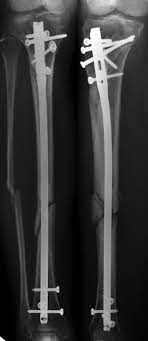

Accident and Trauma Car

event-img-1.png